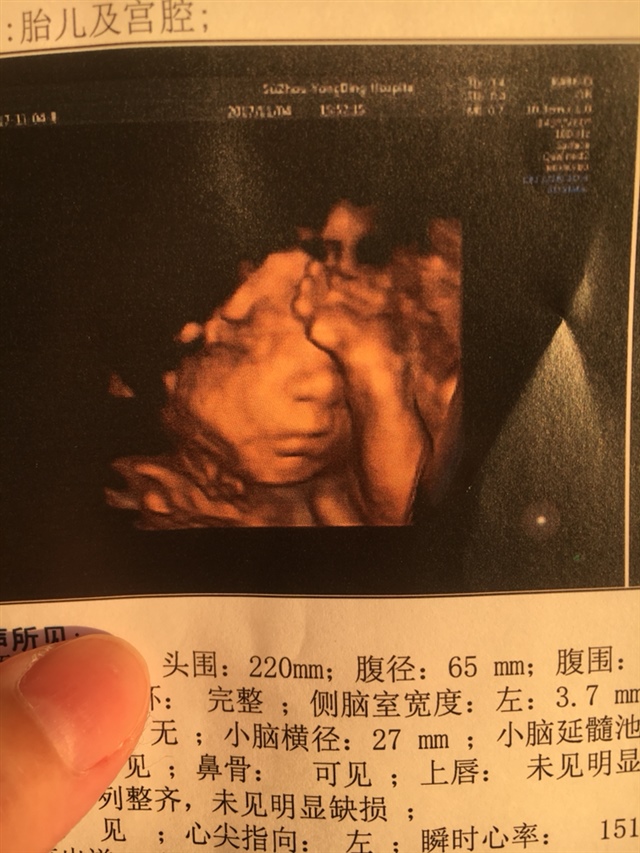

33周我的绕颈两圈

A丫丫童装😛[帖主]:宝爸看到四维单子一个劲的说不好看、不好看…😅